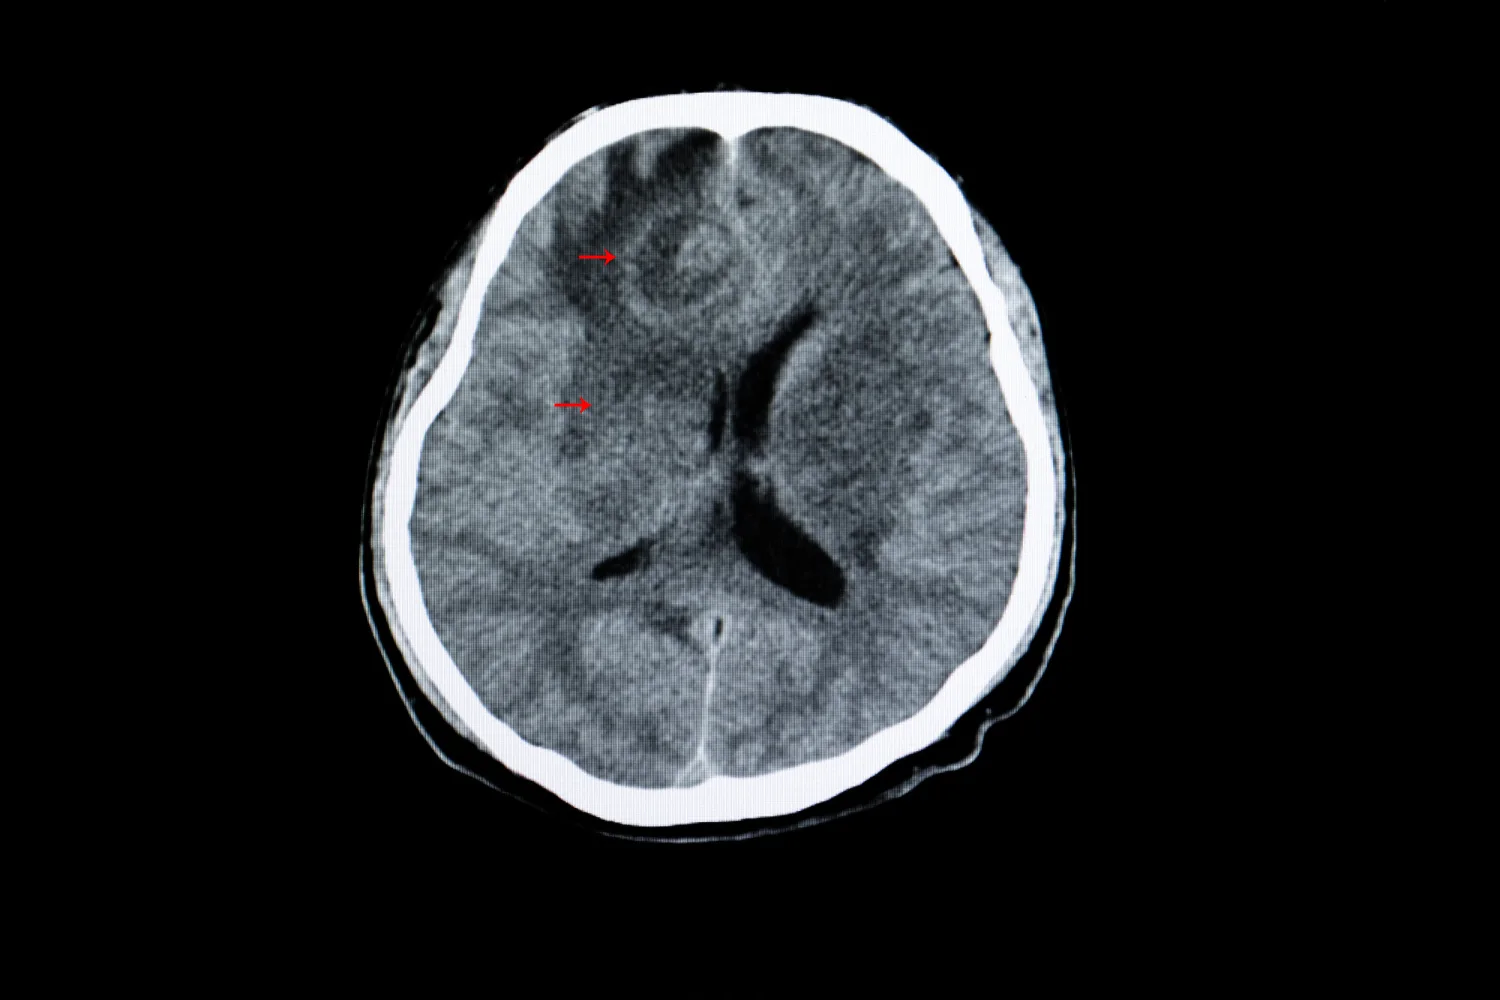

- Toxoplasmose em imunossuprimidos: pacientes portadores de HIV ou que fazem uso de medicamentos imunossupressores têm maior risco de desenvolver formas graves, como encefalite.